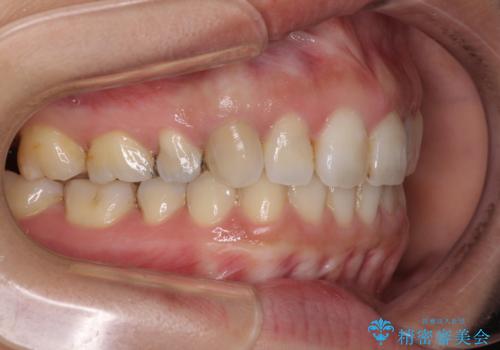

- 上の前歯の捻じれと突出感を気にして来院された患者様です。

目立たない装置を希望とのことで、上顎左右第一小臼歯を抜歯し、インビザラインにて矯正治療を行うこととしました。